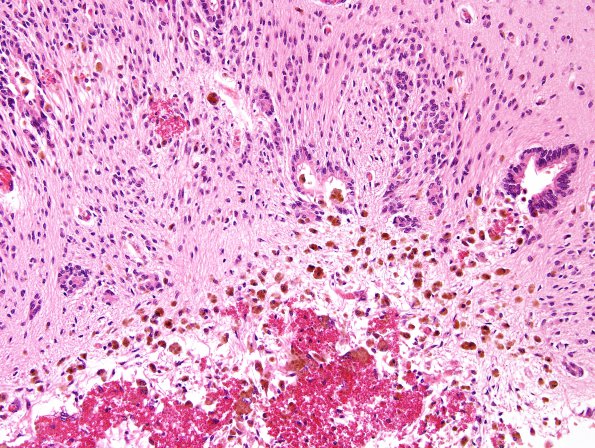

Hydrocephalus, Post-Hemorrhagic

5B4 Hydrocephalus after IVH (Case 5) A10

Higher magnification of image #5B3 (H&E)